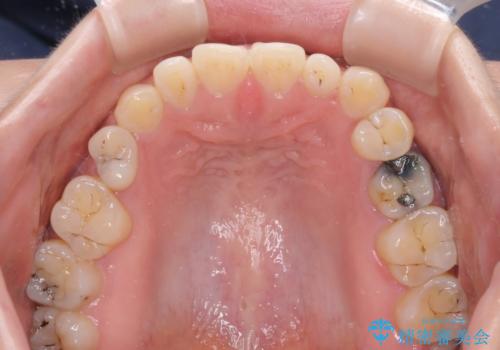

隙間の空いた歯列とボロボロの乳歯 インプラント治療と矯正治療

- 隙間の多い歯列や傾斜した奥歯、むし歯の酷い残存乳歯を気にして来院された患者様です。

上顎のむし歯の酷い残存乳歯は抜歯をし、矯正治療の途中でインプラントを埋入、矯正治療後に補綴治療を行うこととしました。